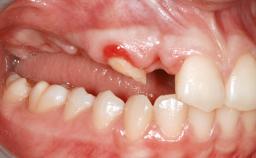

A 45-year-old woman with a completely edentulous maxilla was referred to evaluate the possibility of rehabilitation with an implant-supported prosthesis. This patient was healthy and a non-smoker. She had been wearing a maxillary complete denture opposing a natural mandibular dentition since her twenties. This situation had resulted in progressive resorption of the alveolar ridge, repeatedly creating a need for relining the denture. Twenty years later, despite multiple adaptations and the use of “glues” the denture was unstable and causing the patient psychological and functional discomfort.

Bone Volume Deficient vertically or deficient vertically AND horizontally